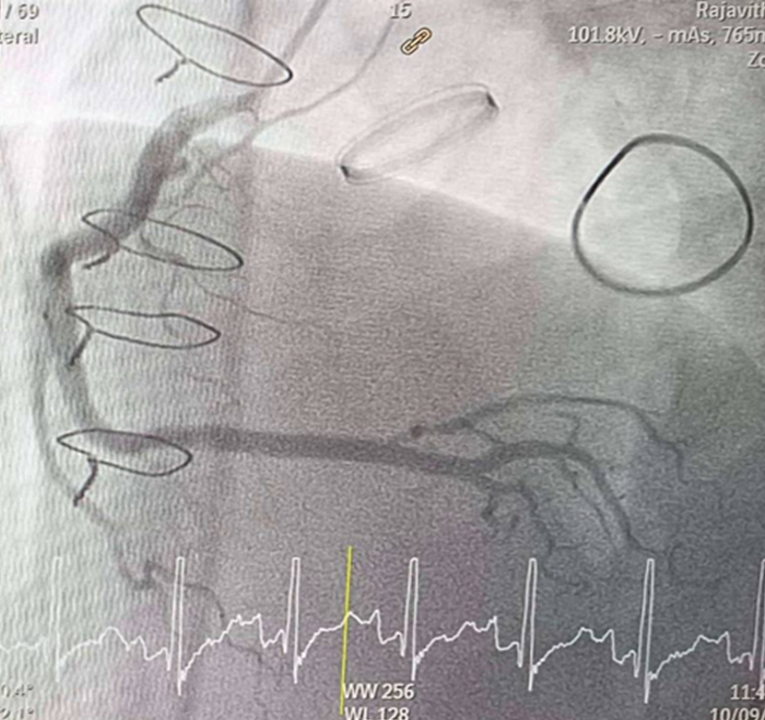

CAG was performed with right femoral approach with JL 4.0/7 Fr, JR 4.0/6 Fr diagnostic catheter showedRight dominantLM : mild irregular, non significant stenosis.LAD : total occlusion mLAD.LCx : mild irregular, non significant stenosis.RCA : non significant stenosis.

Inserted Sion wire and thrombuster to LAD revealed multiple red clots.SC balloon 2.0 x 15 mm, then 2.5 x 15 mm, was inflated at mLAD up to 12 atm. IVUS insertion to LAD revealed vessels’ size LM 5-5.5 mm, pLAD 4-4.5 mm, mLAD 3-3.5 mm with intraluminal thrombus, dLAD 2.75-3 mm. Multiple inflations were done at mLAD with SC balloon 2.5 x 15 mm. After multiple SC balloon inflations, the CAG revealed slow flow phenomenon. Then, the operator performed thrombus aspiration, multiple SC balloon 2.0 x 15 mm inflation and gave IC integrillin 3.4 ml. The final angiogram was acceptable result. The anticoagulant was given after CAG. Chest pain was subsided and hemodynamic parameters remained stable. EKG recorded after angiography showed resolution of ST elevation at V1-3. Later, the patient was discharged with warfarin. The Aortomitral intervalvular fibrosa repair surgery was planned due to embolic complication.